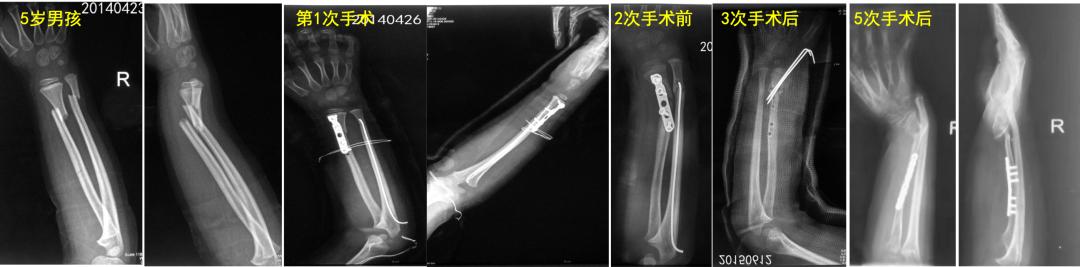

学生:会出啥问题啊? 老师: 对于11岁的孩子来说,切开复位钢板固定,损伤太大,对骨折端愈合微环境影响很大。如果术后管理不当的话,会大大增加骨折不愈合的风险。就像下面例子中的5岁孩子,前后经历了5次手术,反而问题越来越严重……

像下面这个10岁孩子,前臂远端骨折手术后8年,桡骨远端骺板早闭出现严重腕部畸形。所以,需要警惕,儿童“骺板”其实是把双刃剑,保护好了才能利于治疗,一定不能损伤它。